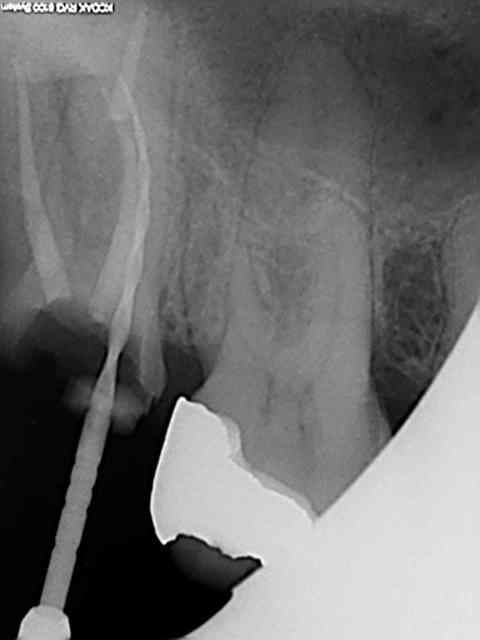

J'ai utilisé le localisateur d'apex , mais bon un radio c'est une radio ...)))

J'ai fait une reprise de TR sur 27 en novembre dernier ; digue, javel, NiTi, pour un bon résultat radio.

Radio cone 25 en place etc....)))) j'avoue je pèche dans le etc !)))